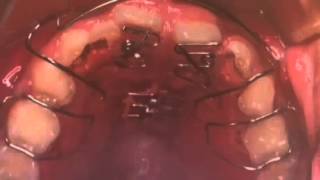

目立った汚れや傷はなく美品です。あくまでも中古品のため、ご理解いただける方のみご購入ください。「臨床医のための床矯正・矯正治療 反対咬合篇」鈴木 設矢定価: ¥ 24000#鈴木設矢 #鈴木_設矢 #本 #自然/医療・薬学・健康